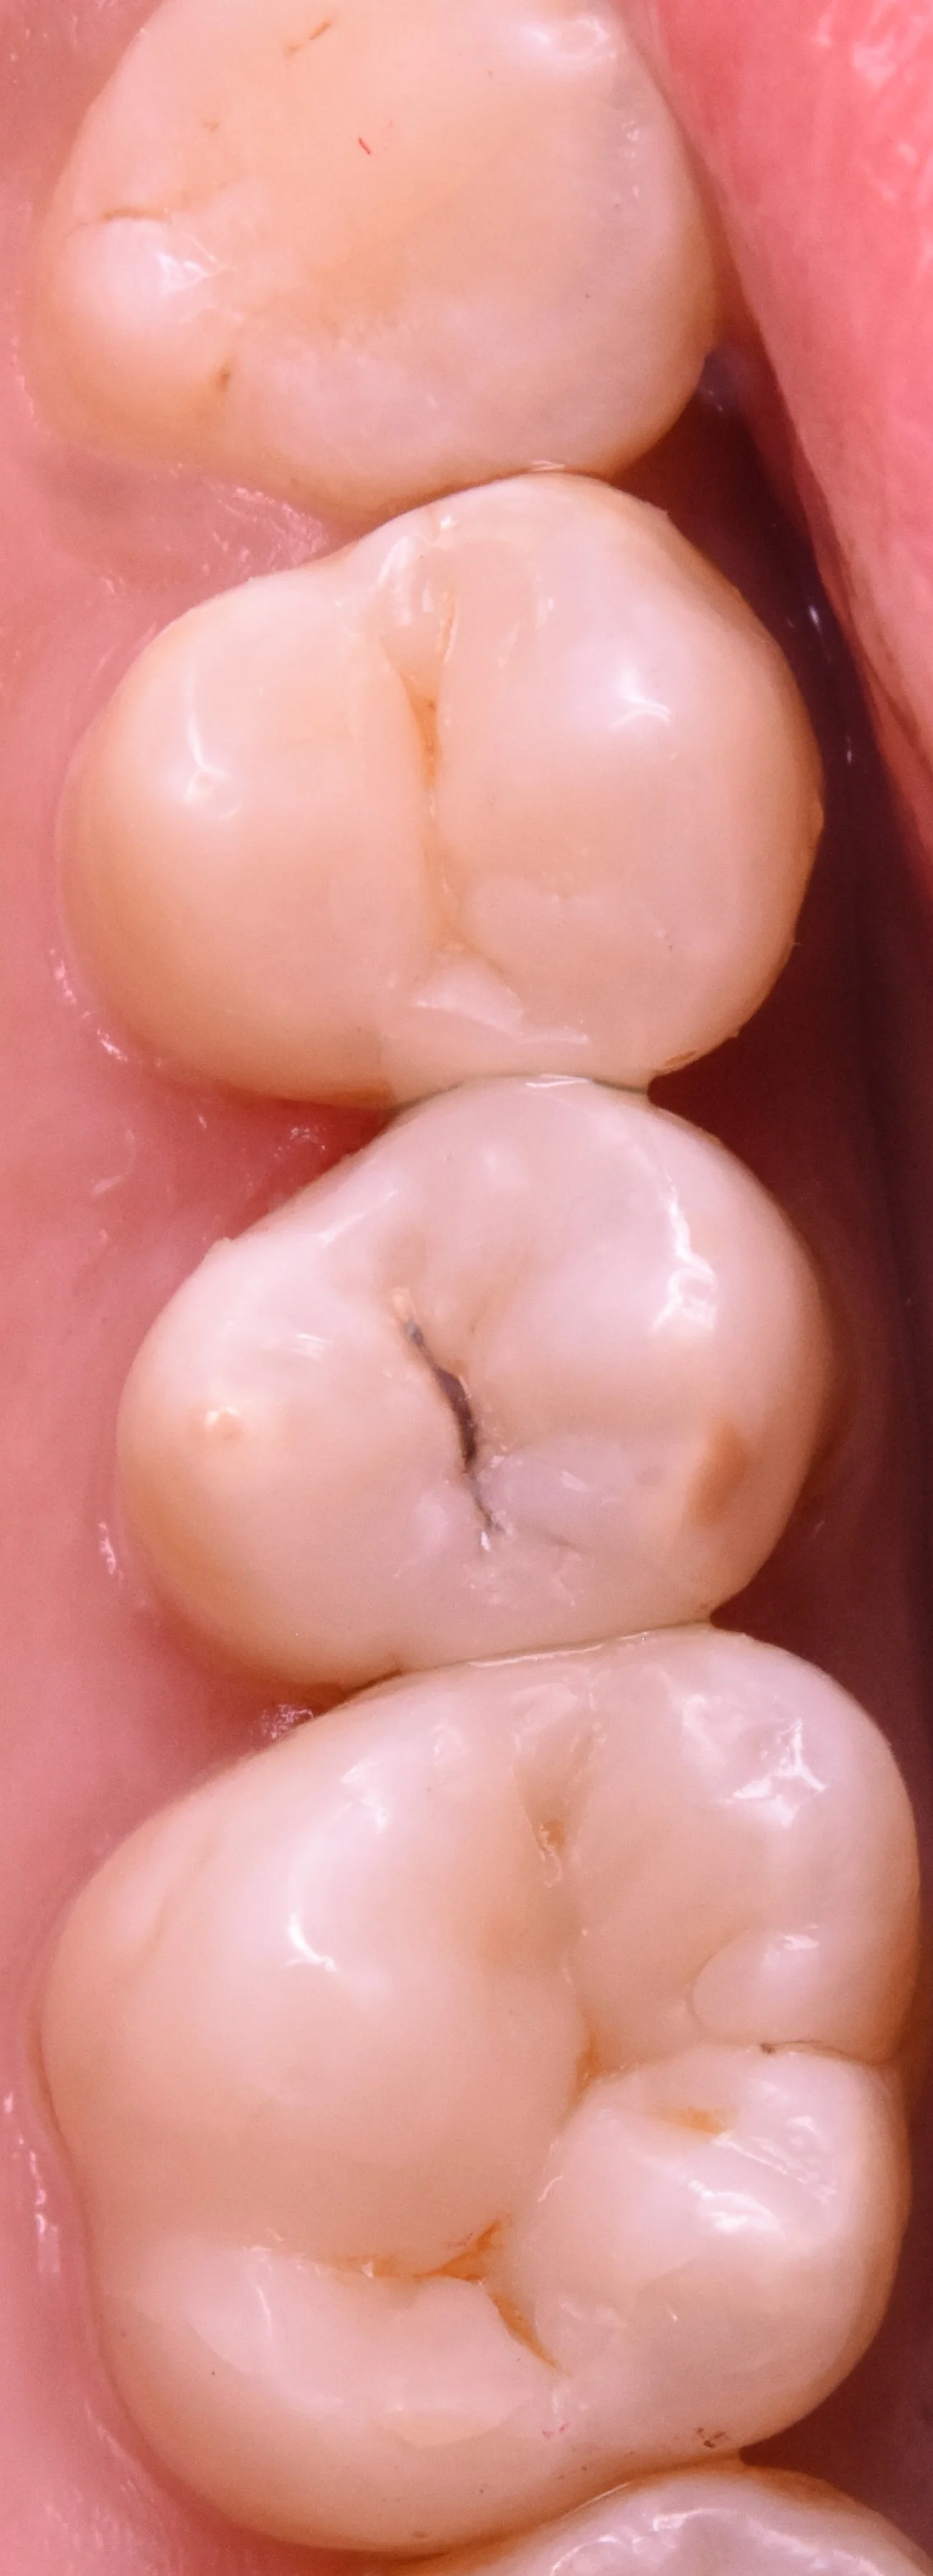

では術前の写真からです。

アマルガムといわれる非常に古い金属が詰められています。

虫歯が見やすくなったのがこちらです。

あからさまに黒いのがわかりますよね?

歯の表面にはエナメル質という層がありますが、その層は透過性が高いため、中の黒い部分が透けて見えていたというわけです。

一番右側の歯についてはエナメル質の感じ的に内面の象牙質部分はほとんどなくなっていると術前の段階で予測できるほどでした。

そして虫歯を取り切ったのがこちらです。

一部着色層は残っていますが、虫歯の部分はすべて取り切れています。

通常であればこの着色層も除去したほうが接着としては有利なのですが・・・

今回それを行ってしまうと神経を抜く危険性があると判断し、一部残しています。

また予想通り、一番右の虫歯はほぼ象牙質が残っていない状況でした。

通法通りこの歯を治療するのであれば全く問題のない神経を抜いた上で全周削って被せ物を入れるしかないです。

また残存している歯の位置的に通常の金属やセラミックの詰め物(インレー)を入れた場合は長期予後は期待できずに歯が割れてしまった危険性が非常に高いです。

そうなると歯の寿命は一気に短くなってしまうので、そういう点でも今回はダイレクトボンディングがベストチョイスでしたね。

そして治療終了後の写真がこちらです。

いかがでしょうか?

比較的違和感なく詰められたかと思います。

個人的には真ん中の歯の溝の色に合わせてステイン(人工的な着色)を入れられたのがよかったかと思います。